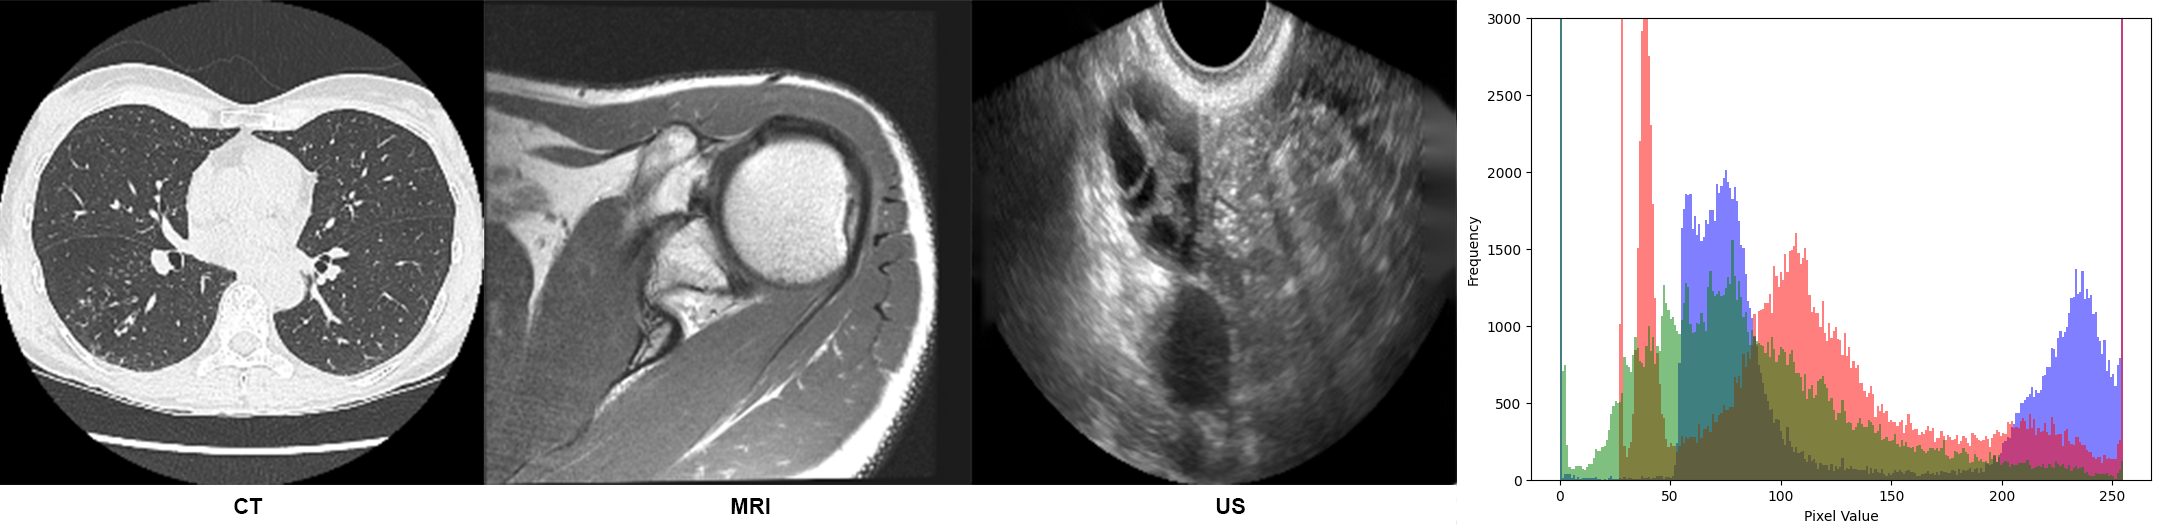

Medical imaging datasets, such as MRI scans, ultrasound images, and CT scans, often exhibit significant heterogeneity and variations in low-level features due to differences in acquisition protocols, imaging modalities, and anatomical regions, an example illustration is in Figure 1. These variations manifest as differences in brightness, contrast, and noise levels, which can be readily discerned even through visual inspection of image histograms. Such low-level distinguishability hinders the learning of high-level semantic relationships. The challenge is to capture and homogenize these low-level image features to improve classifier performance.

Figure 6 presents medical scans with their respective histograms, indicating low-level features and pixel intensity distributions. The stochastic masking operation performed by the policy network modifies the skewness and center of distribution using pixel-wise multiplication, enhancing the image representation for the classifier and achieving a form of homogenization.